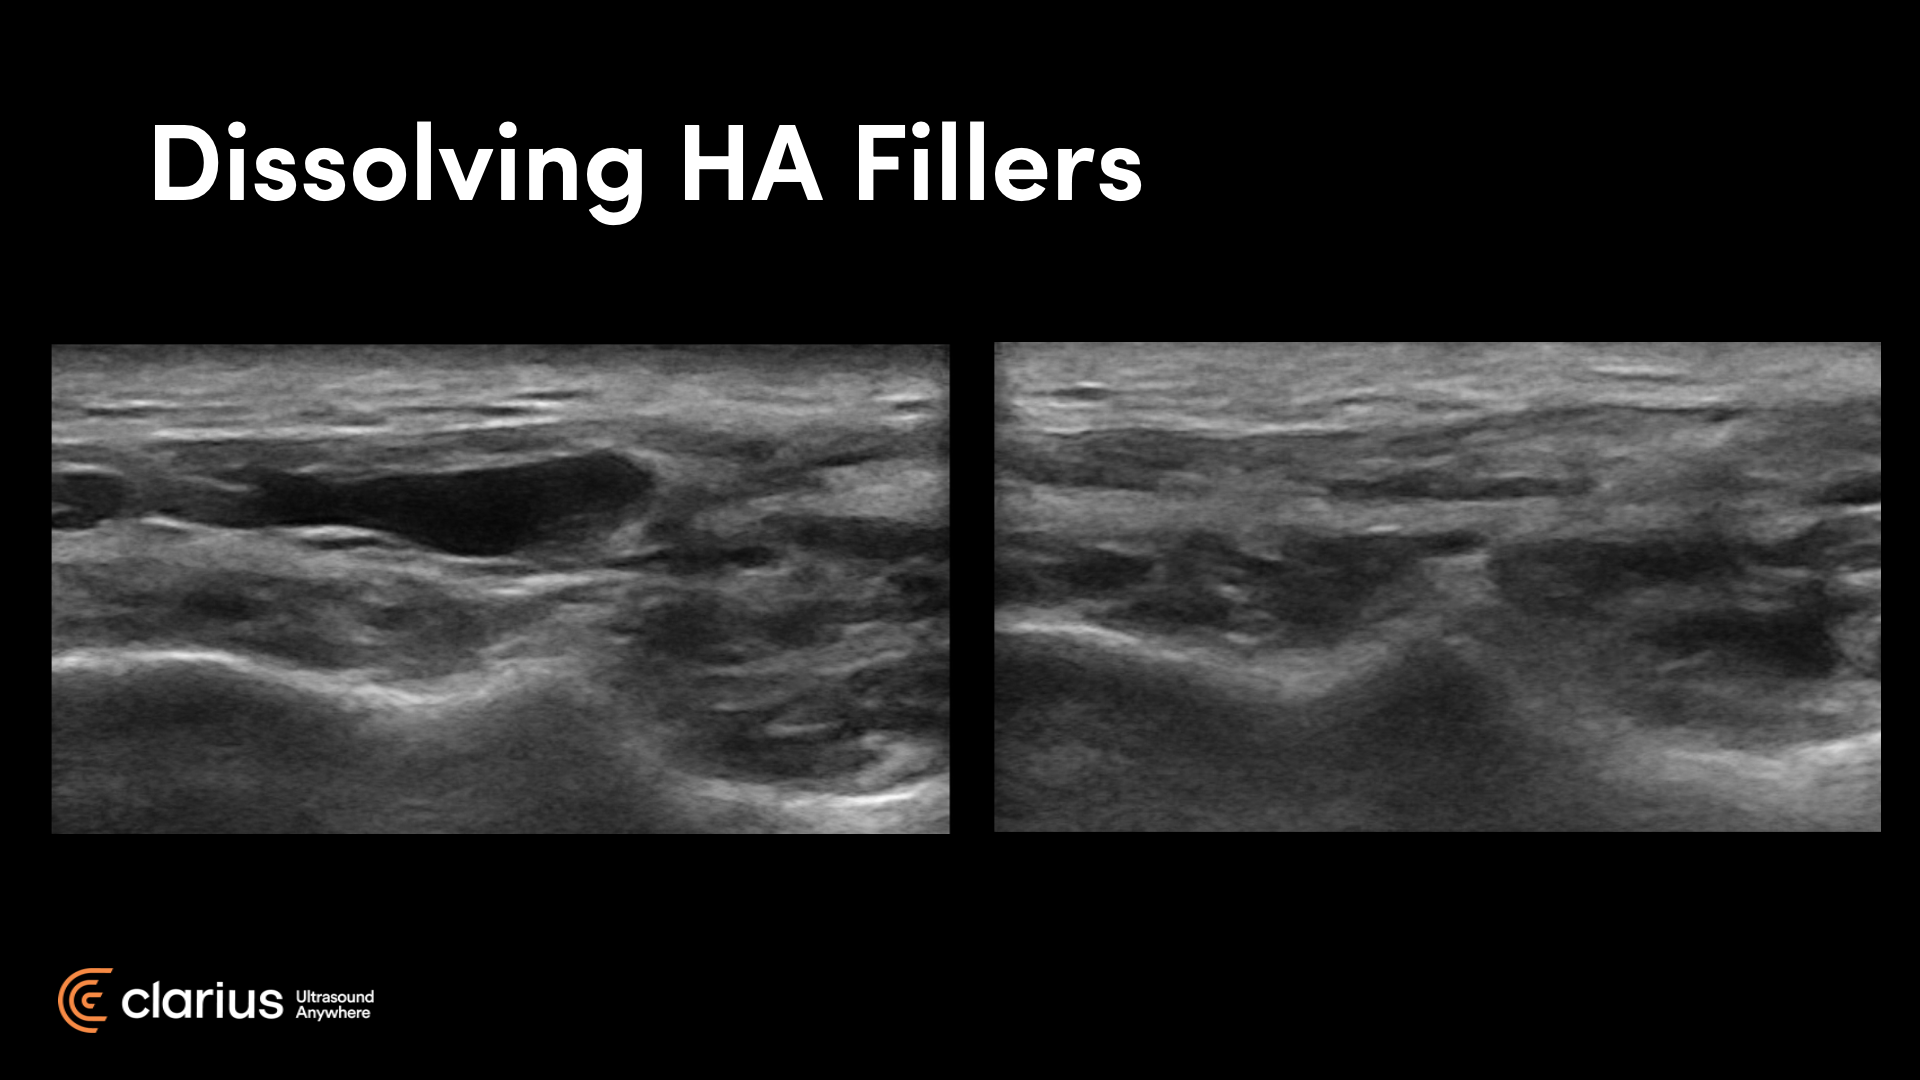

From clarius.com

[VIDEO] Learn How to Use Ultrasound To Treat Dermal Filler Utility Of High-Frequency Ultrasound In Dermal Filler Evaluation Cosmetic medicine has recently shown interest in the use of doppler ultrasound (dus) analysis of the face because of the. Ultrasound imaging may be considered as a valuable tool for evaluating the nature of former dermal filler procedures in. Utility Of High-Frequency Ultrasound In Dermal Filler Evaluation.

Ultrasound Characteristics of Dermal Fillers Clarius Utility Of High-Frequency Ultrasound In Dermal Filler Evaluation Ultrasound imaging may be considered as a valuable tool for evaluating the nature of former dermal filler procedures in. Cosmetic medicine has recently shown interest in the use of doppler ultrasound (dus) analysis of the face because of the. Utility Of High-Frequency Ultrasound In Dermal Filler Evaluation.